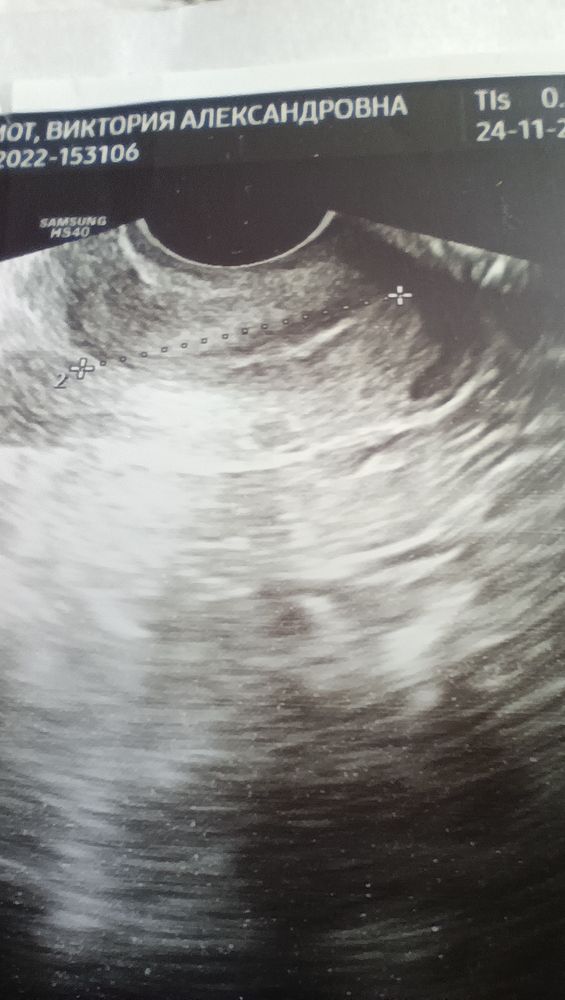

Она начала делать УЗИ, как вдруг мы увидели плодное яйцо, характерное для 5 недели, жёлтое тело есть, но эмбриона ещё не видно.

Сказала что укорочена шейка матки, прописала дюфастон, элевит, фолиевую, много спать, есть много белка.